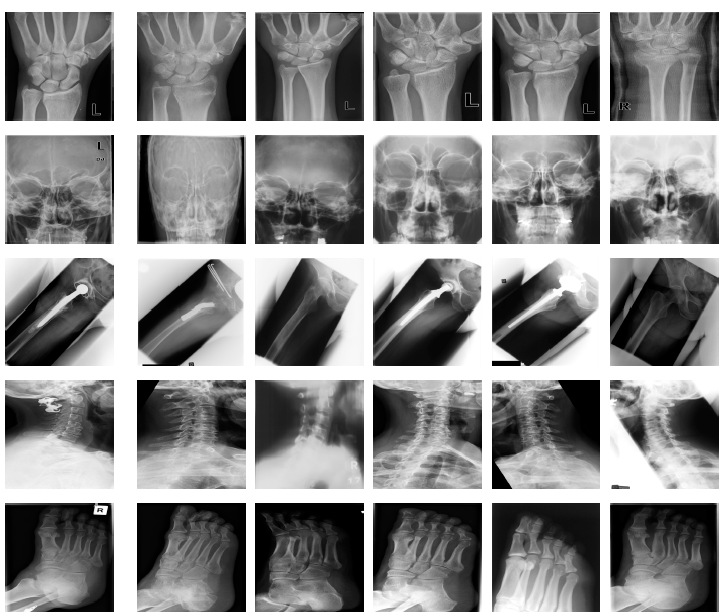

Figure 2 show some sample images from IRMA dataset and their Radon barcodes with 4, 8, 16 and 32 projections applied on input images resized to 64×64646464\times 64.

Figure 2: Five randomly selected images from IRMA dataset and their Radon barcodes with (from top to bottom) 4, 8, 16 and 32 projections.